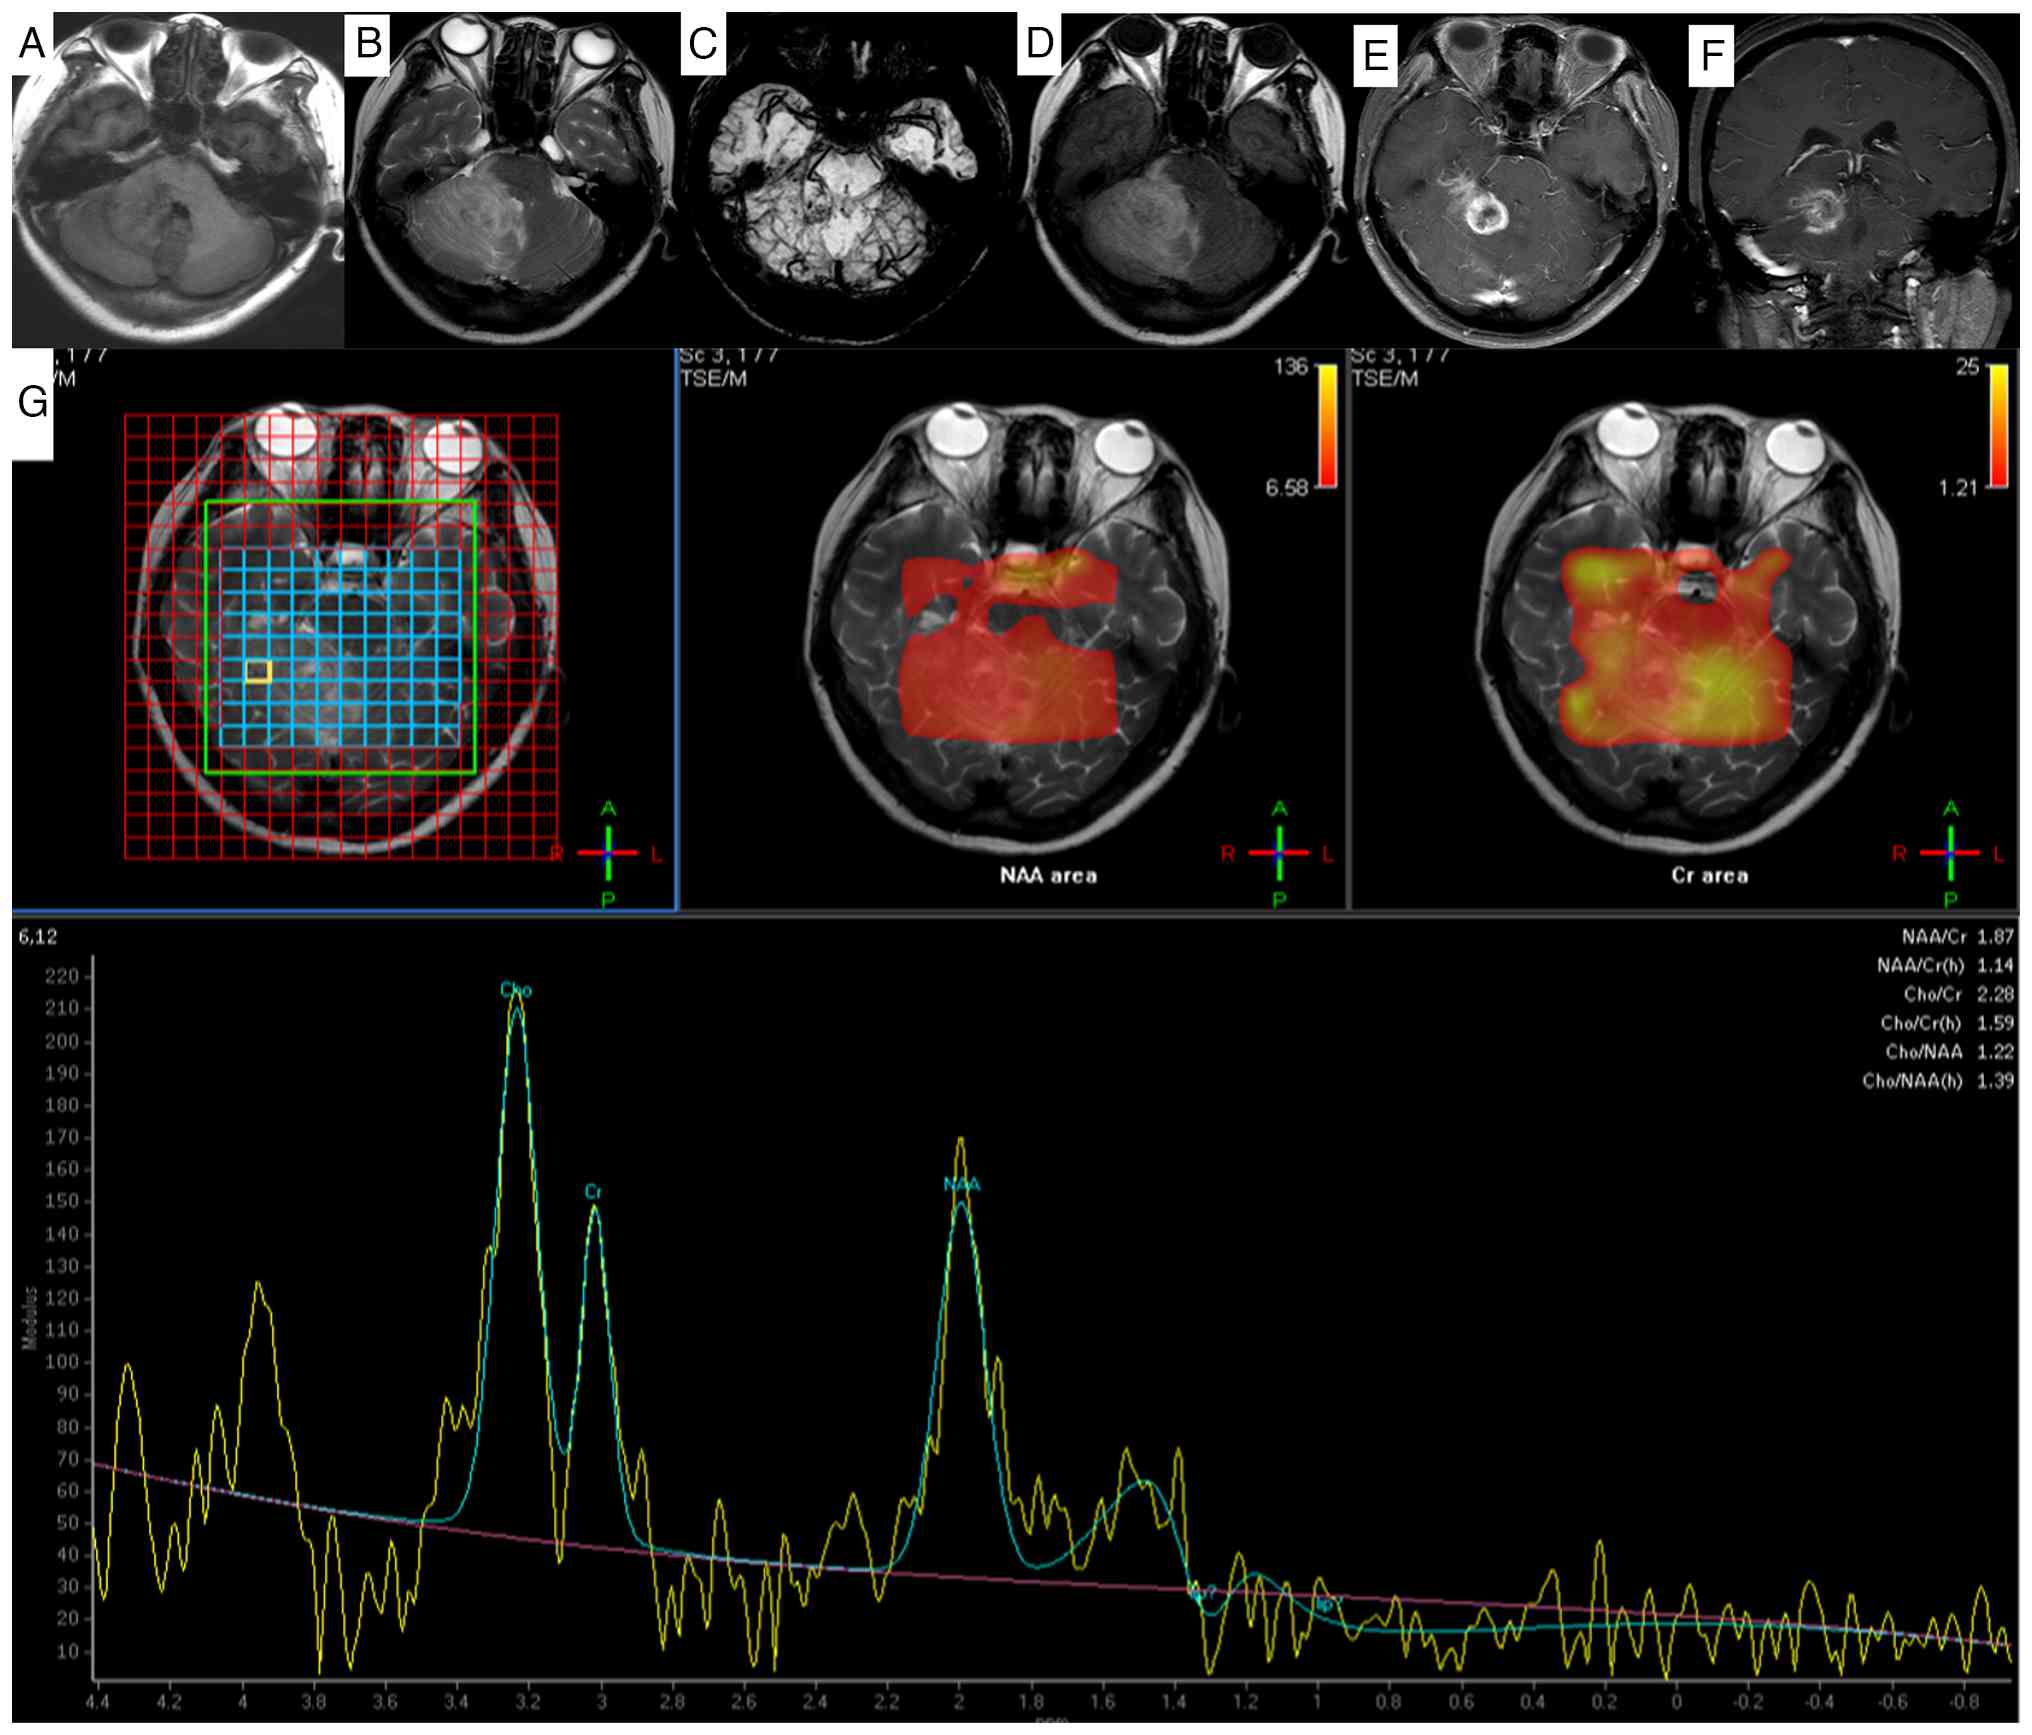

Preoperative brain MRI demonstrated a large (4.0×2.8×2.7 cm), lobulated, mixed-signal-intensity mass occupying the right cerebellar hemisphere and parahippocampal region. The lesion exhibited partial diffusion restriction on diffusion-weighted imaging/apparent diffusion coefficient sequences. Susceptibility-weighted imaging revealed intralesional punctate hypointensities suggestive of microhemorrhages or calcifications. Post-contrast T1-weighted imaging revealed marked heterogeneous enhancement. Significant perilesional edema, manifesting as T1 hypointensity and T2 hyperintensity, was noted in the adjacent cerebellar parenchyma, extending to involve the right brainstem and cerebellar vermis. Mass effect resulted in compression of the fourth ventricle. Magnetic resonance spectroscopy (MRS) within the lesion demonstrated a characteristically elevated choline (Cho) peak and a markedly reduced N-acetylaspartate (NAA) peak, consistent with high cellular turnover and neuronal loss. Patchy slightly prolonged T1 and isointense T1 signals were noted in the right cerebellar hemisphere and right parahippocampal region (Fig. 1A). On T2-weighted imaging, the same region exhibited slightly prolonged T2 signals interspersed with small patchy slightly shortened T2 signals (Fig. 1B), with a lobulated mixed-signal mass identified in this area. Susceptibility-weighted imaging revealed punctate hypointense foci within the lesion (Fig. 1C). Fluid-attenuated inversion recovery imaging showed hyperintense signals in the lesion (Fig. 1D). Marked heterogeneous enhancement of the lesion was seen on axial (Fig. 1E) and coronal (Fig. 1F) post-contrast images. The lesion involved the right brainstem and cerebellar vermis, with compression of the adjacent fourth ventricle and brainstem. MRS of the lesion area revealed a decreased NAA peak, a significant elevation of the Cho peak and a nearly unchanged creatine (Cr) peak (Fig. 1G).

Magnetic resonance imaging findings of

gliosarcoma in the right cerebellar hemisphere and right

parahippocampal region. (A) In the right cerebellar hemisphere and

right parahippocampal region, patchy slightly hyperintense and

isointense signals on T1-weighted imaging were observed. (B) On

T2-weighted imaging, slightly hyperintense signals were noted,

mixed with small patchy slightly hypointense signals. (C)

Susceptibility-weighted imaging demonstrates punctate hypointense

foci within the lesion. (D) Fluid-attenuated inversion recovery

imaging shows hyperintensity. The lesions exhibited obvious

inhomogeneous enhancement on (E) axial and (F) coronal images. The

lesion involves the right portion of the brainstem and cerebellar

vermis, with compression of the adjacent fourth ventricle and

brainstem. (G) The peak value of NAA in the lesion area was

decreased, the peak value of Cho was significantly increased, and

the peak value of Cr remained basically unchanged. MRI, magnetic

resonance imaging; NAA, N-acetylaspartate; Cr, creatine; TSE/M,

turbo spin echo/magnetization.

Figure 1.

Magnetic resonance imaging findings of gliosarcoma in the right cerebellar hemisphere and right parahippocampal region. (A) In the right cerebellar hemisphere and right parahippocampal region, patchy slightly hyperintense and isointense signals on T1-weighted imaging were observed. (B) On T2-weighted imaging, slightly hyperintense signals were noted, mixed with small patchy slightly hypointense signals. (C) Susceptibility-weighted imaging demonstrates punctate hypointense foci within the lesion. (D) Fluid-attenuated inversion recovery imaging shows hyperintensity. The lesions exhibited obvious inhomogeneous enhancement on (E) axial and (F) coronal images. The lesion involves the right portion of the brainstem and cerebellar vermis, with compression of the adjacent fourth ventricle and brainstem. (G) The peak value of NAA in the lesion area was decreased, the peak value of Cho was significantly increased, and the peak value of Cr remained basically unchanged. MRI, magnetic resonance imaging; NAA, N-acetylaspartate; Cr, creatine; TSE/M, turbo spin echo/magnetization.